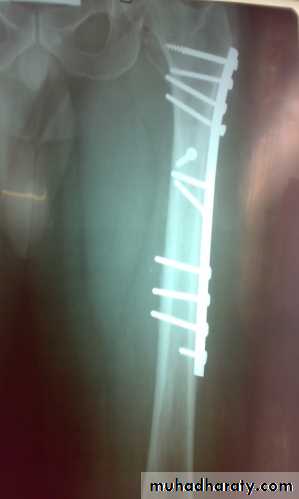

Fixation of femoral shaft fracture

closed fractures: by Open reduction and internal fixation, this will decrease the systemic complications..

Definitive treatment